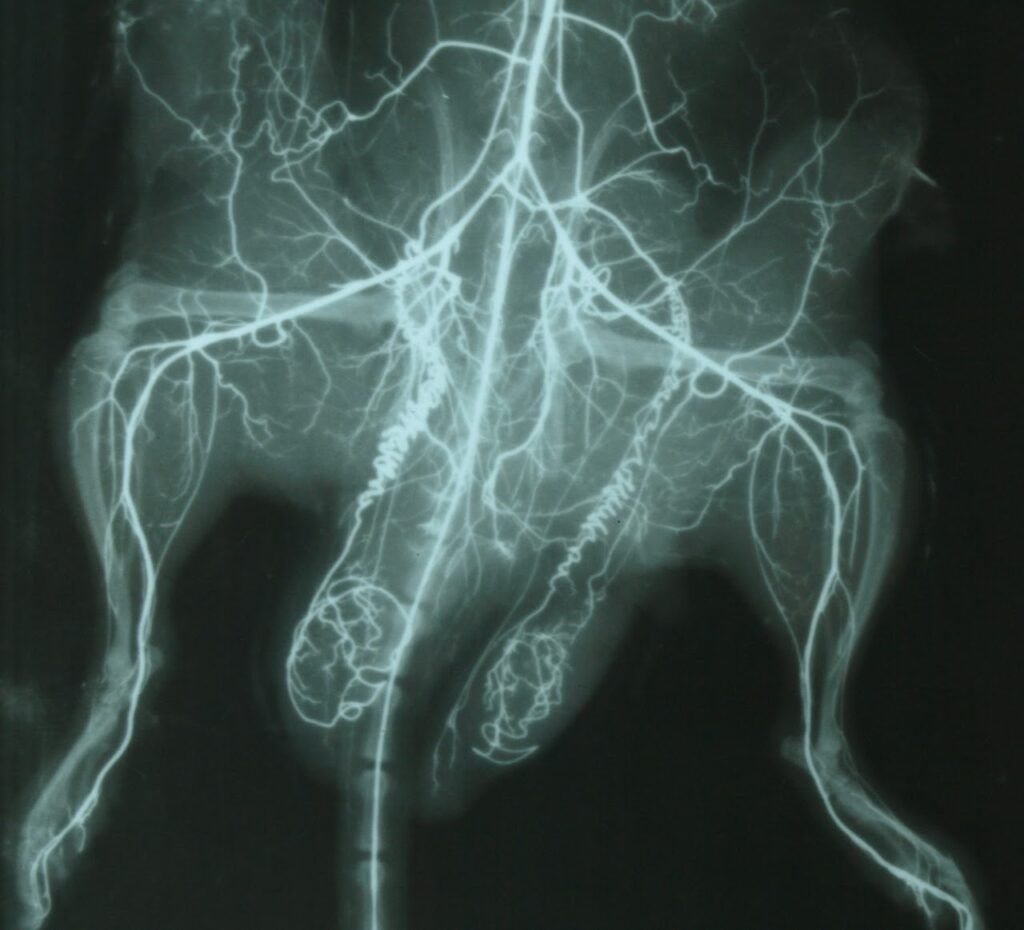

Студенти опрацьовують методику наливки судинного русла щура рентгенконтрастною речовиною ( свинцевим суриком)

Результат проведеного експерименту: рентгенангіографія артерій експериментальної тварини